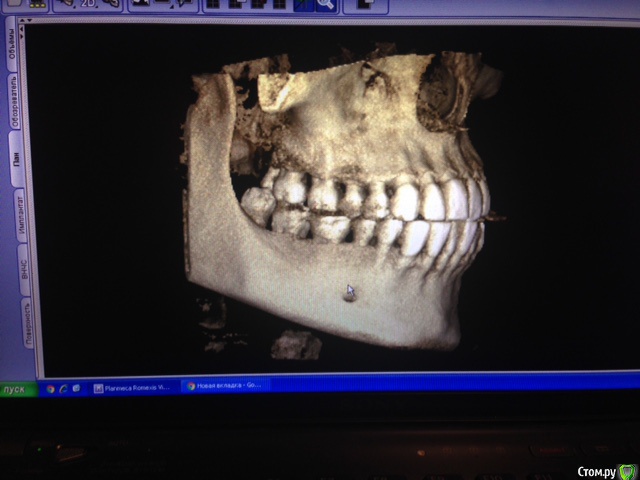

Hellae Опубликовано 17 января, 2016 Поделиться Опубликовано 17 января, 2016 Просьба откликнуться специалистов что делать в моей ситуации. У меня уже год шатается 4 зуб верхней левой челюсти. Длительное время постоянно кровил. Удалять сказали еще в феврале 2015, но я все никак не решалась т.к. вместе с ним требуется удаление еще и 5-го зуба рядом с ним. Плюс ко всему это связано с генерализованным парадонтитом(так мне сказали) на фоне которого и расшатался 4-й зуб. Сейчас имплантолог сказал надо удалить 2 зуба (4 и 5) подсадить костную ткань и ждать когда она приживется, потом ставить импланты, а пока кость нарастает сделать лоскутные операции.Снимки у мня только КТ февраль 2015 я сфотографировала панораму и прицельный двух зубов может можно как то по ним увидеть. Ссылка на комментарий